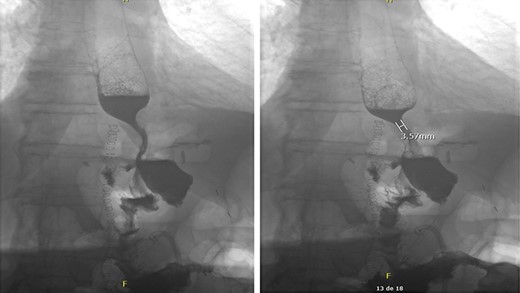

The patient mentioned after surgery that her symptoms started after ingesting a significant quantity of maize. In the postoperative period, the patient developed a fungemia to Candida glabrata that was treated accordingly. No intra-abdominal complications occurred. A barium swallow was performed in the postoperative period to assess the integrity of the esophagojejunal and jejunojejunal anastomoses. No leak was objectified (Fig. 2). The patient was successfully discharged home after a hospital stay of 20 days. The feeding jejunostomy tube was removed 2 months later. No outpatient complications were noted except mild deconditioning that required physical therapy.

Intact esophagojejunal and jejunojejunal anastomoses on barium swallow.